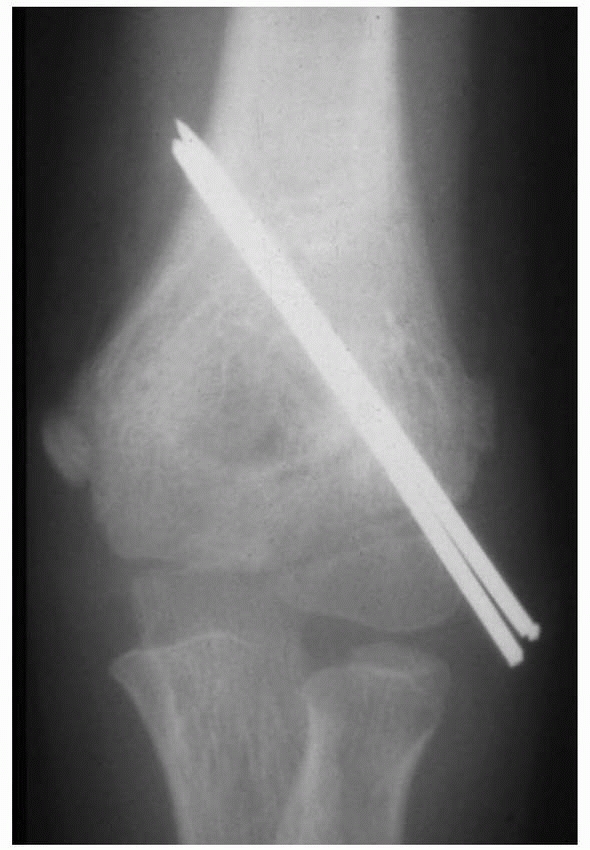

![]() |

FIGURE 15-9 Stage II fracture of the lateral condyle. A.

AP radiograph shows 4 mm of displacement of the metaphyseal segment; however, the fracture was stable by stress examination and arthrography. B. Four weeks after percutaneous pinning, the fracture is healed. |